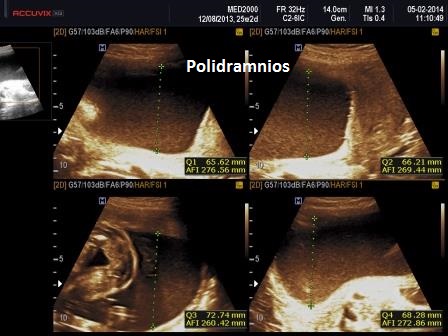

Le lesioni caratteristiche a carico del SNC sono rappresentate  da idrocefalo grave, con ventricoli aperti nello spazio subaracnoideo, ipoplasia cerebrale, anomalie della linea mediana e del setto pellucido (agenesia del corpo calloso); possono essere presenti encefalocele occipitale, una caratteristica conformazione del forame magno “key-hole shaped”, mandibola piccola e naso malformato, labio-palatoschisi. Caratteristica è la polidattilia postassiale alle mani e preassiale ai piedi (l'alluce duplice è altamente caratteristico, quasi esclusivo, di questa condizione morbosa). Segnalati anche piede torto e difetti cardiovascolari (difetti del setto atriale; atrio unico). Come ha segnalato lo studio di Salonen e coll. (1981) condotto su 28 neonati di 18 famiglie, l'esito abituale della gravidanza è la nascita di feto morto o morte in epoca neonatale.

La Diagnosi Prenatale si basa su: 1) assenza di movimenti attivi fetali; 2) polidattilia postassiale alle mani; 3) polidattilia preassiale ai piedi;  4) idrocefalia; 5) polidramnios.